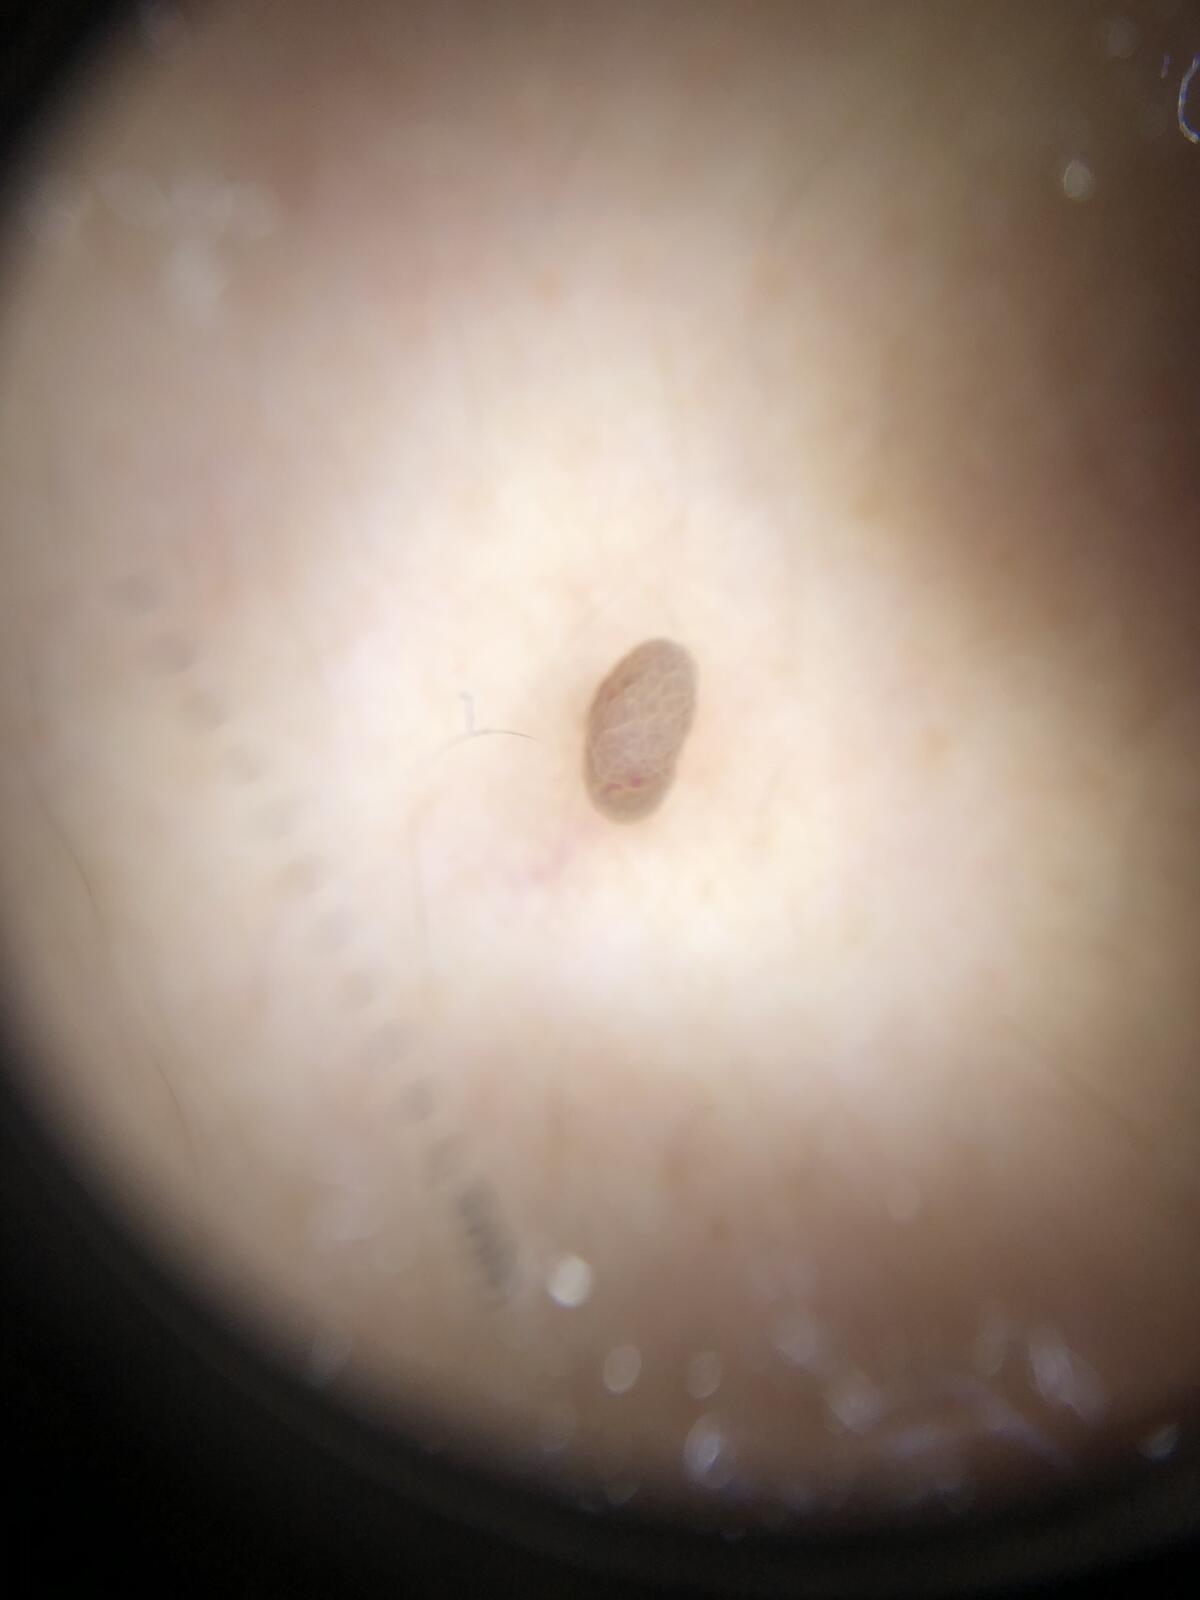

软纤维瘤又名纤维上皮细胞性息肉、皮赘、软瘊,是一种有蒂的良性肿瘤 。 分为三个类型①皱纹状小丘疹,多发,质软,直径1~2 mm,好发于颈部; ②丝状软纤维瘤,单发或多发,质软,宽约2 mm,长约5 mm; ③有蒂软纤维瘤,单发,质软,直径约1.0 cm或更大,好发于躯干下部、腹股沟,呈肤色或色素增多。 采用电离子、激光、火针等物理方法治疗。参考文献综述略。